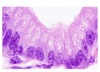

Aspecto histológico glândula mucosa?

Histologia: Tecido Epitelial Glandular

Mucosas?

Secretam mucinógenos.

(células caliciformes, glândulas salivares e palato)